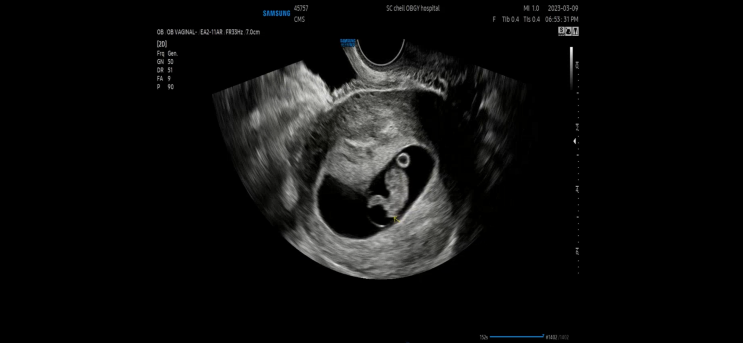

38주 5일_대학병원일기 2: 입원하세요

2025.06.27

하릴없이 공휴일을 보냈다. 각 병원에 대해 엄청 검색을 하고 기저질환과 출산의 상관관계에 대해 검색을 ...